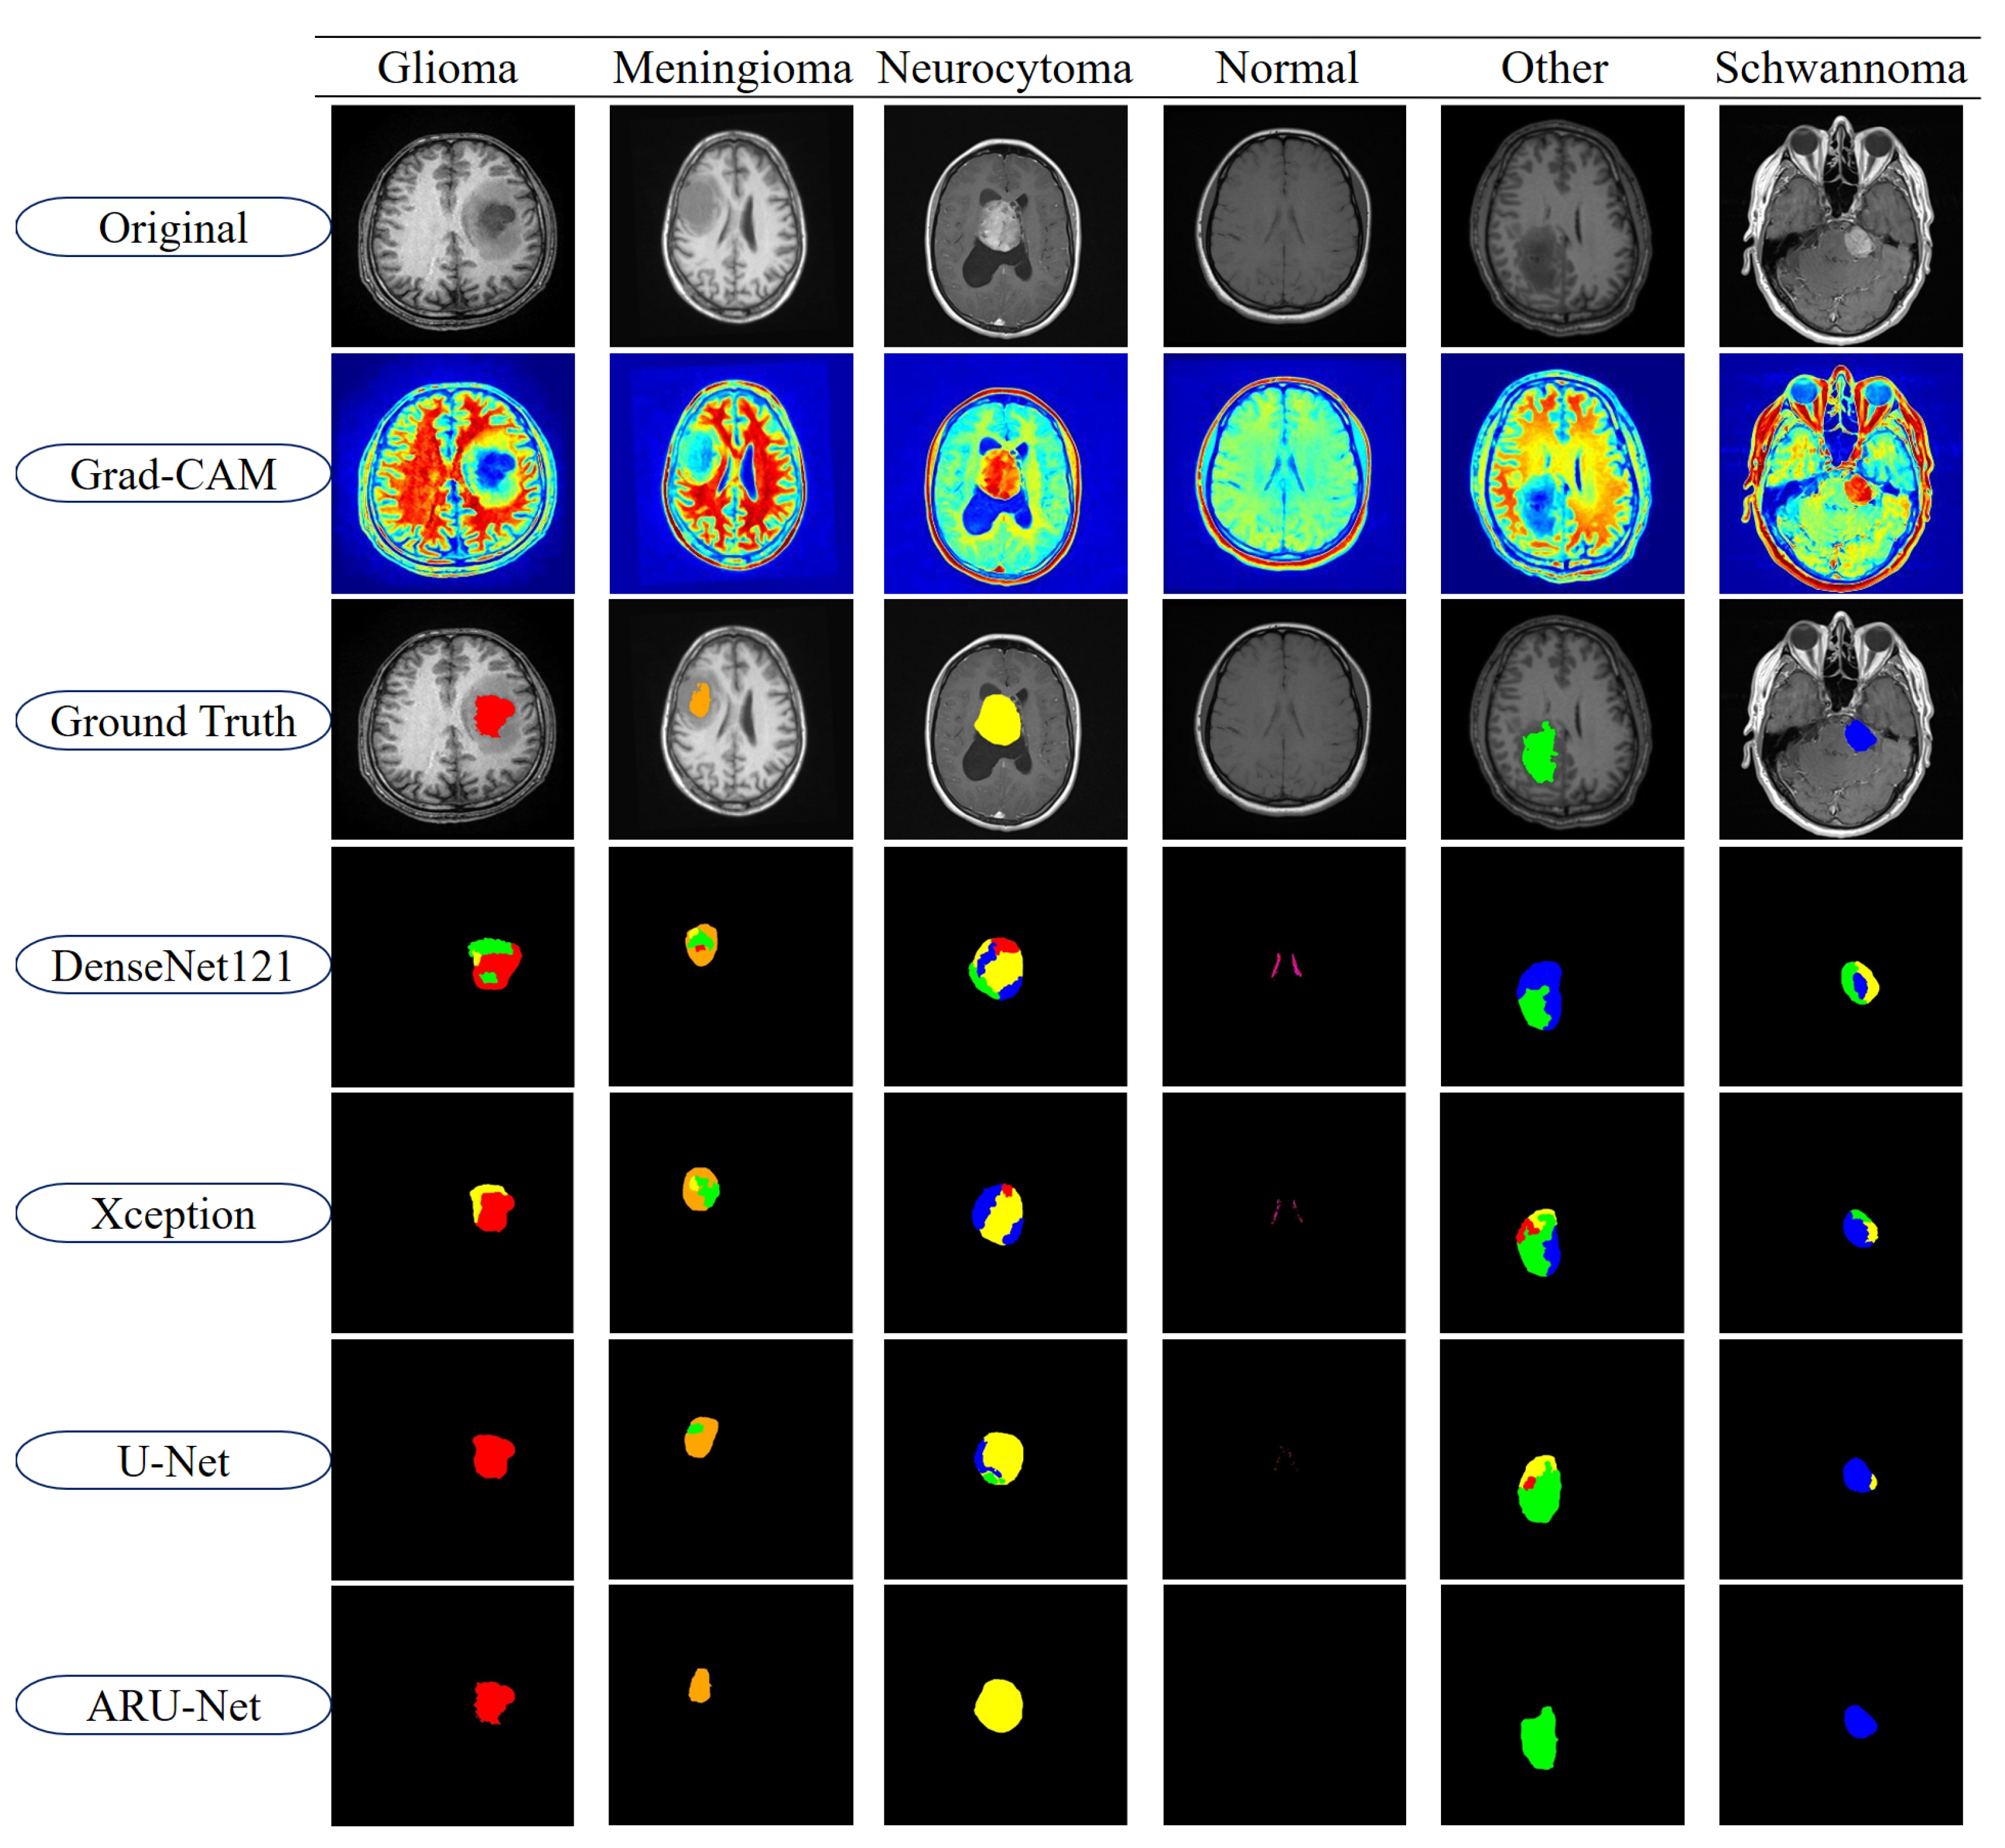

In this study, a three-stage pre-processing strategy was employed to improve the success of the segmentation model in MRI-based brain tumor images. First, CLAHE enhances the visibility of tumor structures by locally increasing the contrast between the tumors and surrounding tissues. However, this process also carries the risk of introducing noise; therefore, a powerful denoising method such as non-local means denoising is then applied to suppress random noise in the image. In the final stage, edge-preserving smoothing is performed with a Linear Kuwahara filter to preserve the edge details while smoothing the overall textural image. This sequence both corrects for density artifacts and helps compensate for noise that may occur after CLAHE application. The CLAHE, Denoising, and Kuwahara filter sequence is the ideal approach for suppressing post-contrast noise and preserving edges. This three-stage approach aimed to increase the segmentation performance of the model while preserving the anatomical accuracy of the tumor. Low-frequency illumination/bias (intensity inhomogeneity) in MRI images, resulting from coil and magnetic field imbalances, can affect segmentation and contrast processing. Therefore, algorithms applied in the pre-processing steps aim to address this imbalance [44].

In the linear variants, weighted sums of subregion averages were computed, yielding more stable outcomes. A 5 × 5 square window was employed. Consequently, the linear variants demonstrated greater robustness against block selection instability. Figure 2 illustrates sample images from each pre-processing stage of the BTMRII dataset.

To further highlight the differences between models, segmentation outputs are visualized in Figure 11. The figure displays representative examples from each of the six tumor classes in the BTMRII dataset. For each case, the original input, Grad-CAM heatmaps, ground truth annotations, and segmentation predictions from DenseNet121, Xception, U-Net, and ARU-Net are shown. The color-coded masks illustrate class-specific tumor regions and highlight discrepancies between the model predictions and ground truth boundaries.

As illustrated in Figure 11, DenseNet121 and Xception exhibited noticeable misclassifications and boundary inconsistencies, particularly in glioma and meningioma cases. These models frequently produced incomplete or noisy segmentations, leading to reduced reliability in clinical applications. U-Net demonstrated considerably stronger segmentation capabilities, successfully capturing most tumor structures with relatively smoother boundaries. However, minor deviations, including boundary misalignments and occasional regional misclassifications, were observed in classes such as Meningioma and Other. In contrast, the proposed ARU-Net model achieved highly accurate and robust segmentation across all tumor classes. Its predictions were characterized by smooth contours, precise tumor boundaries, and minimal false classifications, even in challenging cases where other models failed. ARU-Net’s enhanced attention mechanism allowed it to adapt effectively to intra-class variability, providing superior generalization and stability. This advantage was particularly evident in complex tumor regions, where ARU-Net closely replicated the ground truth shapes without over-segmentation or under-segmentation.

Figure 2. Sample images of each pre-processed stage from the BTMRII dataset.

Figure 11. Segmentation results of the models for BRMRII dataset.